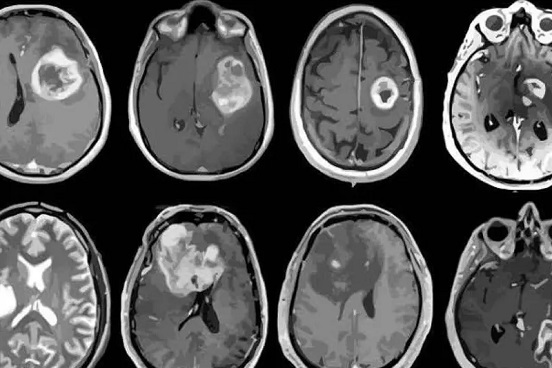

Una niña de 10 años, ciudadana estadunidense, quedó sin acceso a su tratamiento para cáncer cerebral luego de que su familia fuera detenida y deportada a México mientras viajaban a Houston en busca de atención médica. Sus padres y cuatro hermanos también fueron expulsados, dejando a la menor sin cuidados esenciales.

El pasado 4 de febrero, la niña, que aún lucha contra los efectos de una cirugía para extirpar un tumor, fue detenida junto a su familia en un puesto de control migratorio.

Antes de la detención, la niña tomaba medicación para prevenir convulsiones, necesarias tras su cirugía. Ahora, en México, ha quedado sin atención médica adecuada.